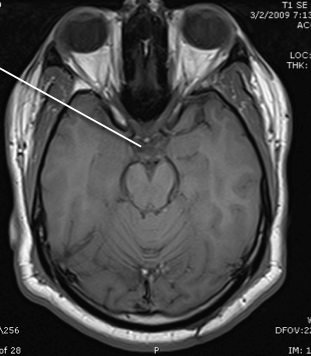

tegmentum of the pons

basis of the pons